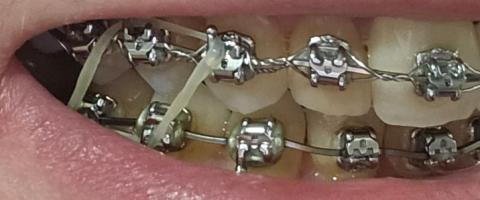

This close-up image shows fixed orthodontic braces with elastic chains (power chains) engaged across multiple brackets. Elastic chains are commonly used to close spaces and consolidate tooth alignment. Mild plaque accumulation is visible around brackets and wire, which is typical during active orthodontic phases and requires focused hygiene.

Upper teeth fitted with metal brackets and archwire

Elastic chains connecting adjacent brackets

Teeth appear intact without visible fractures

Primary concern involves orthodontic mechanics and hygiene around appliances

Metal brackets bonded to teeth

Elastic chains applying continuous force

Archwire engaged and stable

Mild plaque deposits near bracket margins

No visible ulceration or acute infection in this image

Elastic chains appear intact and evenly tensioned

Brackets and wire properly seated

No visible breakage or displacement

Gingival margins visible but not severely inflamed

Risk of gingival irritation if plaque persists

No signs of abscess or ulceration